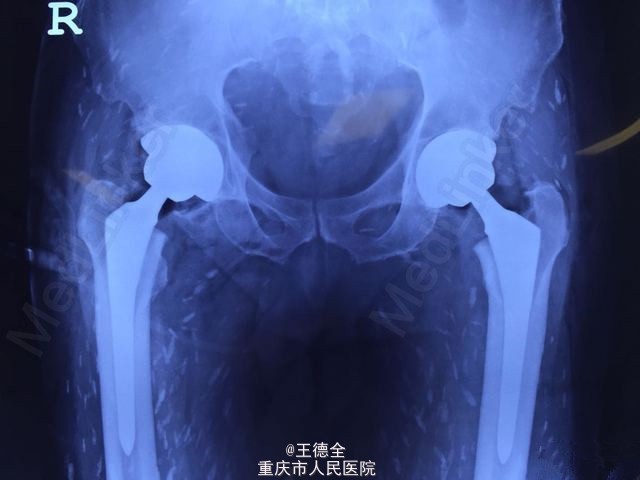

【密集恐惧症慎入】囊虫病感染+双髋置换

患者因囊虫病大剂量激素治疗后股骨头坏死,施行双髋关节置换 。